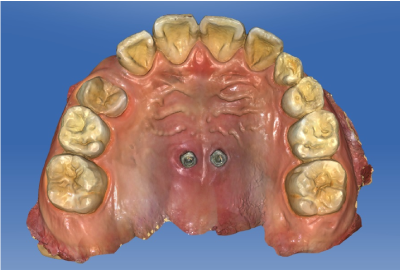

Clinical example

The patient was a 10-year-old boy with insufficient space for canine eruption, and therefore distal movement of maxillary molars was performed. Two mini-screws were inserted in the hard palate (Figure 3). The impression of the heads of the mini-screws, palatal gingiva, and all teeth was taken with an intraoral scanner (Figure 4). Virtual planning of the SHU-lider device was performed by using a CAD software (Figure 5 and 6). Based on the digital design, the coupling, connector and molar bands were printed three dimensionally with metal alloy utilizing a laser-melting machine and manufactured in a custom-made manner. The SHU-lider device were placed on a three-dimensional printed model (Figure 7). The connector and the guide made of stainless-steel wire were welded together. The molar bands were bonded to the bilateral first molars and the coupling were fixed to the heads of the mini-screws. It can be fixed at a predetermined position in the oral cavity (Figure 8). After maxillary molar distal movement, it is possible to cut the anterior part of the guide short. Because there is no superstructure in the anterior center part of the palate, the tongue is less uncomfortable, and myofunctional therapy of the tongue can be performed.

Figure 3. Two mini-screws positioned in the palate

Figure 4. Image taken by intraoral scanner after placement of mini-screws